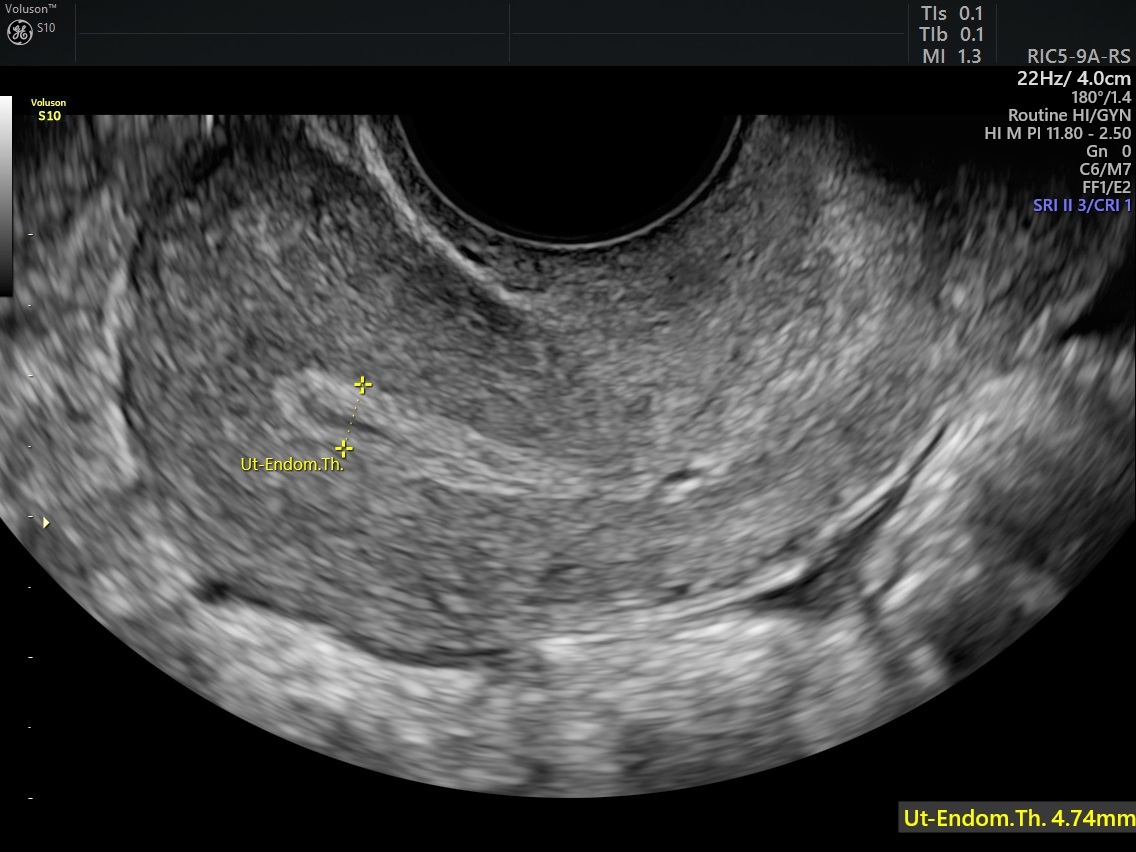

Ultrasound Imaging Of Uterus Demonstrating Endometria vrogue.co

] Ultrasound image showing thickened endometrium Download Scientific Thickened Uterine Lining Bleeding This is the layer of cells that line the inside of your uterus. It can cause vaginal bleeding. This may cause uncomfortable symptoms for. Endometrial hyperplasia is a thickening of the endometrium which is the womb (uterus) lining. The most common sign of hyperplasia is abnormal uterine bleeding. In some women, this can. If you have any of the following,. Thickened Uterine Lining Bleeding.

Ultrasonography showing thickened endometrium (white line) Download Thickened Uterine Lining Bleeding It can cause vaginal bleeding. A pelvic ultrasound is the key diagnostic tool for measuring the. This is the layer of cells that line the inside of your uterus. This may cause uncomfortable symptoms for. While risk factors vary, some conditions that cause too much of the hormone estrogen can lead to endometrial hyperplasia. Endometrial hyperplasia is a thickening of. Thickened Uterine Lining Bleeding.